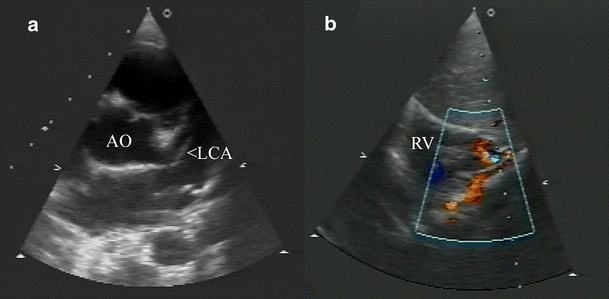

Two-dimensional ECHO images show (a) an enlarged left main coronary artery and (b) a tortuous vessel draining into the right ventricular apex (AO aorta, LCA left coronary artery, RV right ventricle)